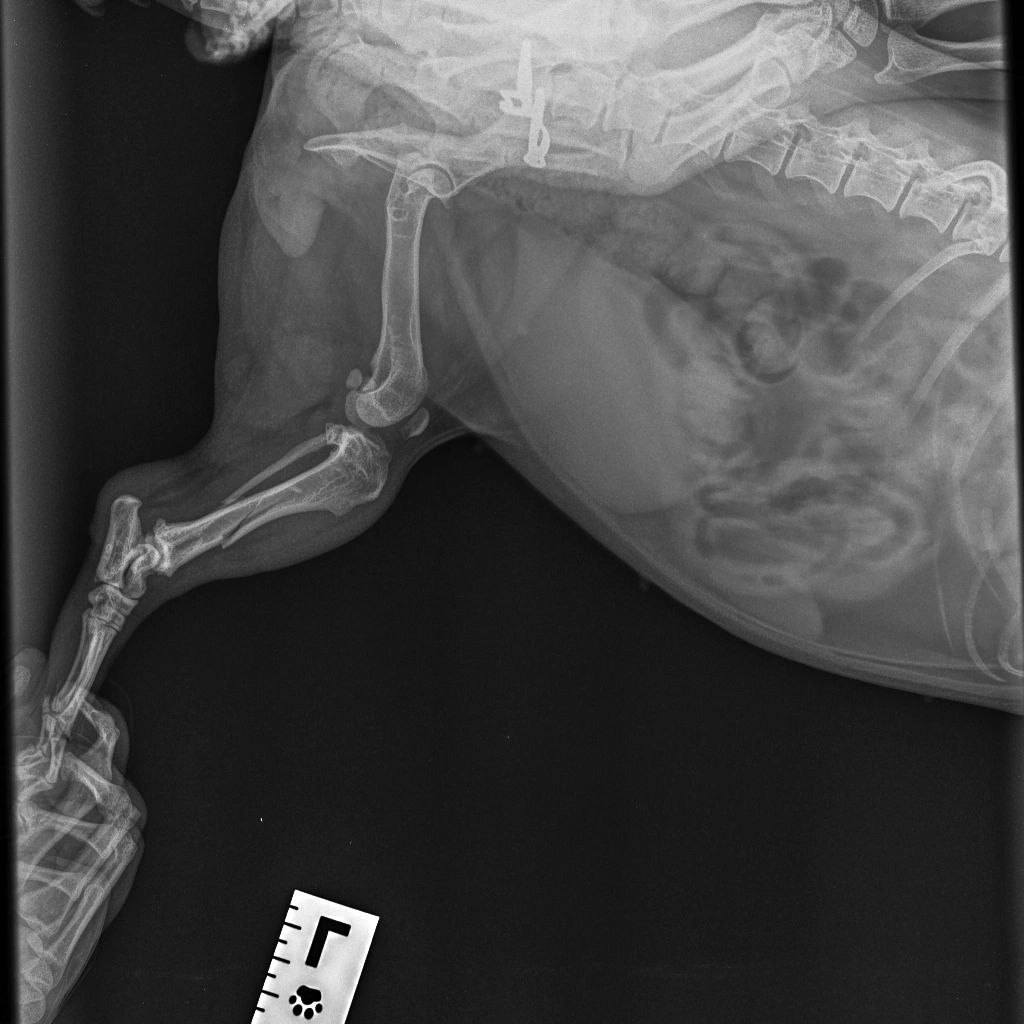

Сломалась лапка у собаки. Уже завтра иду к хирургу на операцию, тут всё срочно, т.к. переломы много времени не дают, не хочется собаку оставлять хромой до конца жизни.